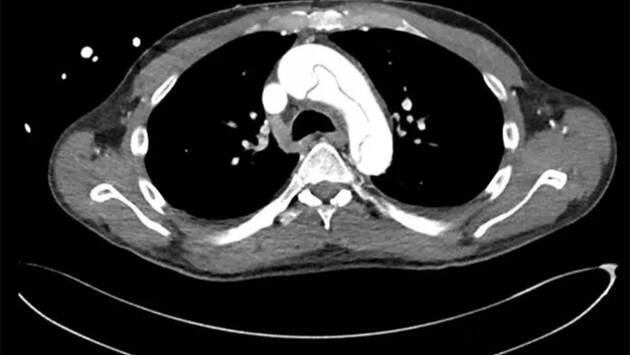

Сообщается, что мужчина вызвал скорую помощь, когда после мастурбации почувствовал, что у него сводит челюсти и покалывает в руках. Врачи были озадачены симптомами пациента и поначалу предположили у него тяжелый случай инфекционного заражения крови. Однако проведенные ими анализы и исследования показали, что у мужчины расслоение аорты — разрыв крупнейшей артерии в организме, сопровождающийся сильной кровопотерей и сердечной недостаточностью.

По данным издания, этот случай примечателен тем, что у пациента не было боли в груди, одышки, повышенного потоотделения, тошноты, потери сознания и других симптомов, характерных для расслоения аорты. В отчете врачей отделения неотложной медицинской помощи больницы Маунт-Синай в Нью-Йорке (США) отмечается, что только 6,4 процента людей с этой патологией не испытывают острой боли в области грудины. Также, по мнению специалистов, необычно, что у мужчины после мастурбации выступили слезы.